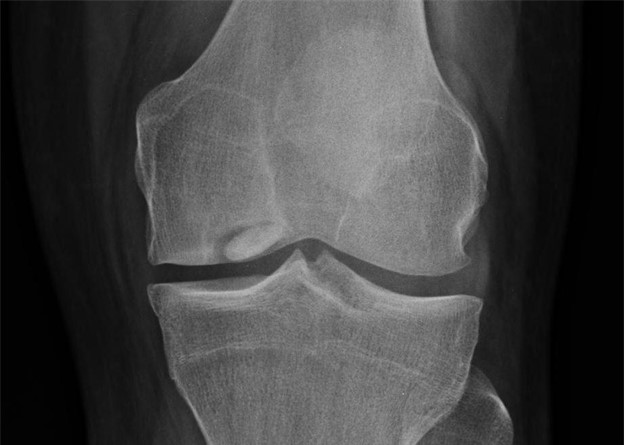

Case courtesy of Dr. Maulik S. Patel, Radiopaedia.org. From the case rID: 10668